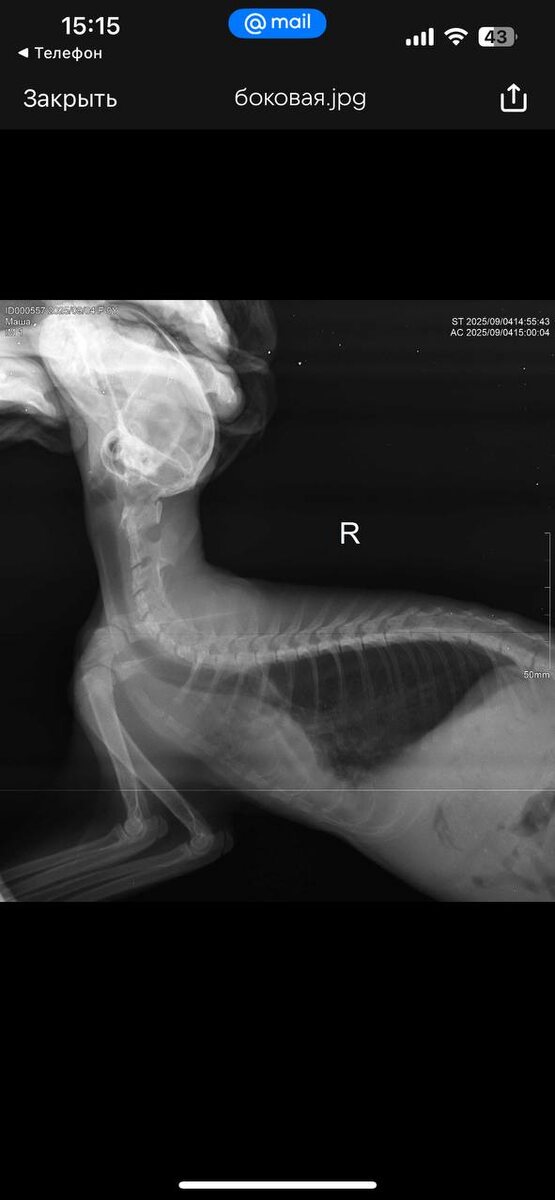

Друзья доброе утро! Новости по новой малышке 🙏🏻. Я ее назвала Машенька . Вчера сделали рентген . По нему начальная стадия отека легких и предположительно диафрагмальная грыжа около сердца . Диагноз пока предположительный . Мы продолжаем лечение и сидим в кислородном боксе . Через неделю надо будет переделать рентген.

Вчера сделали рентген . По нему начальная стадия отека легких и предположительно диафрагмальная грыжа около сердца . Диагноз пока предположительный . Мы продолжаем лечение и сидим в кислородном боксе . Через неделю надо будет переделать рентген.